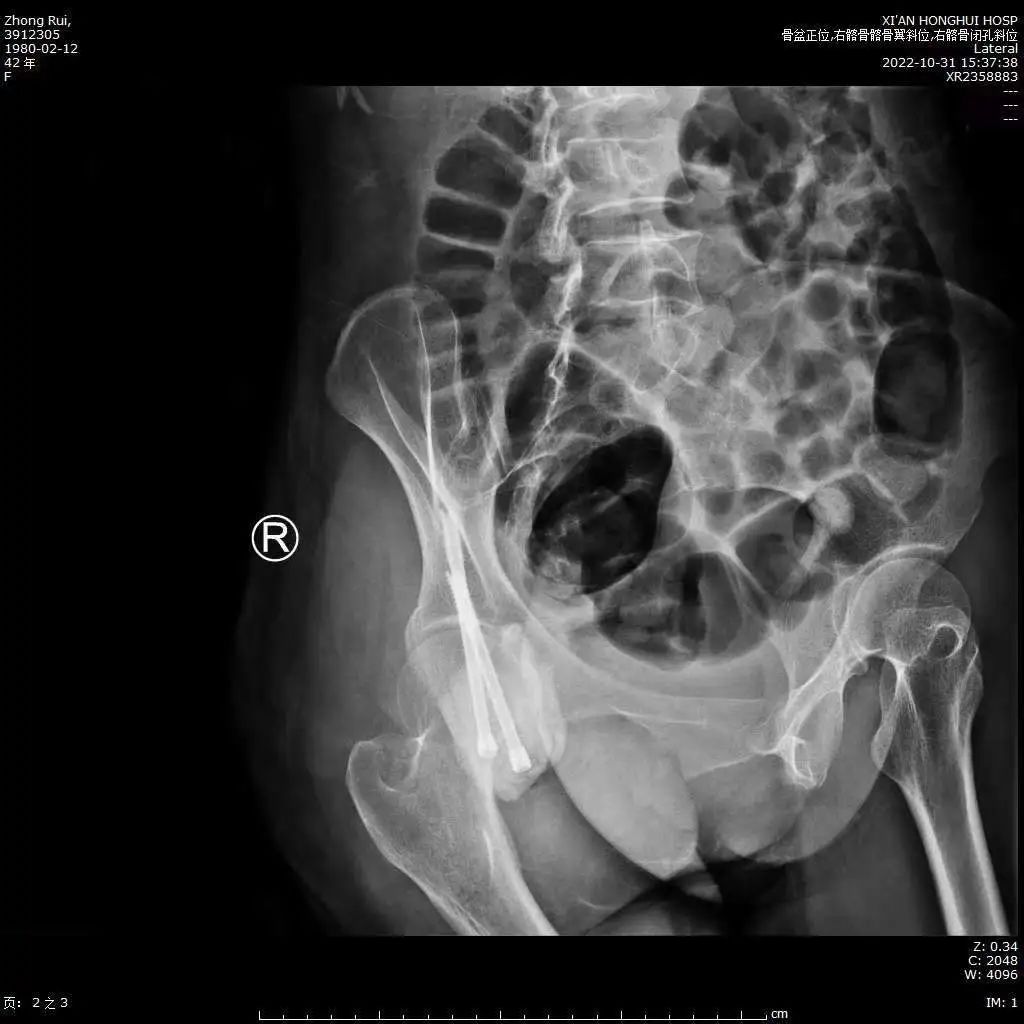

42岁女子小王(化名)因右侧臀部出现疼痛,伴功能障碍半年多,来到西安市红会医院就诊,完善CT及MR检查发现,右侧坐骨巨大肿瘤,肿瘤后侧缘紧紧压迫坐骨神经、盆腔血管;内侧缘及前缘临近直肠、阴 道、尿道等盆腔内脏器仅6-9mm。患者接受病灶穿刺活检,病理结果显示为右侧坐骨软骨肉瘤2级。

(术前核磁共振显示骨盆肿瘤)